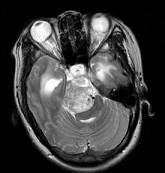

问题 女,32岁,头痛、右侧肢体功能障碍约1年,声间嘶哑,饮水呛咳,请根据所提供图像,选择最可能的诊断()

选项 A.(斜坡)脑膜瘤 B.(斜坡)脊索瘤 C.(斜坡)神经鞘瘤 D.(斜坡)软骨瘤 E.(斜坡)海绵状血管瘤

答案 C